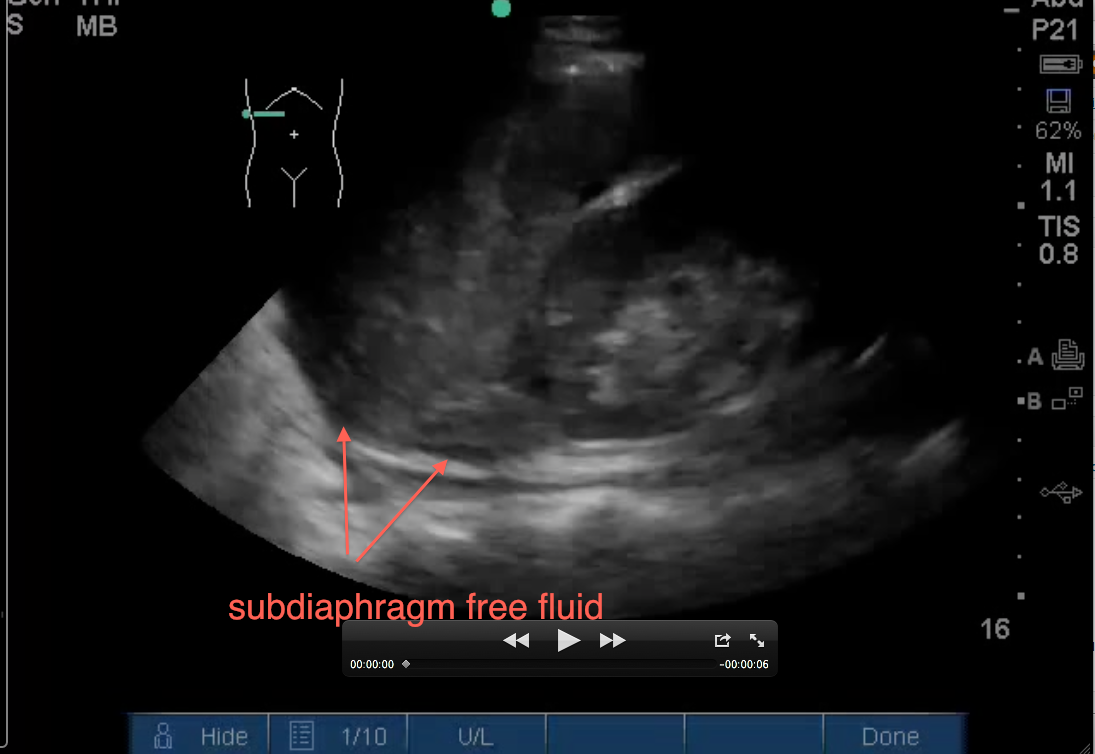

2. Evaluate below the diaphragm… to evaluate for intraperitoneal fluid. If you increased your depth for #1 above, you will need to adjust it back. Black fluid below the diaphragm between it and the liver is abnormal as seen below: